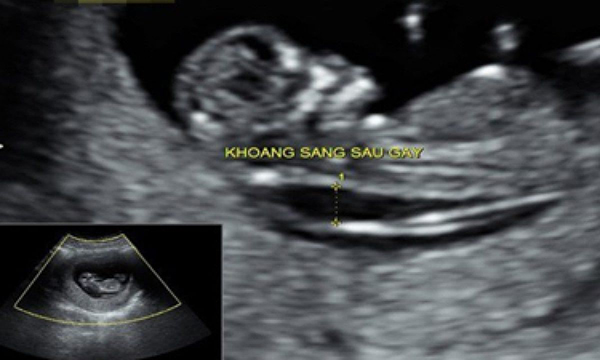

Độ mờ da gát chính là khoảng sáng sau gáy, thể hiện sự kết tụ của chất dịch dưới da vùng gáy, bác sĩ có thể đo chỉ số này vào tuần thứ 11 đến 14 của thai nhi. Việc đo độ mờ giúp bác sĩ chẩn đoán chính xác khả năng mắc bệnh down của bé, nếu có khả năng mắc bệnh thì mẹ cần làm thêm xét nghiệm sàng lọc trước sinh.

Trong trường hợp thai nhi có kích cỡ dao động từ 45mm đến 84mm thì độ mờ da gáy bình thường sẽ dưới 3,5mm, đây là chỉ số quan trọng giúp bác sĩ xác định được 75% nguy cơ trẻ bị Down.

+ Trong trường hợp thai được 11 tuần tuổi thì độ mờ da gáy bình thường là 2mm

+ Trong trường hợp thai nhi được 12 tuần tuổi thì chỉ số tiêu chuẩn sẽ dưới 2,5mm

+ Trong trường hợp thai nhi được 13 tuần tuổi thì độ mờ tương ứng là 2,8mm

Bác sĩ sẽ kết luận thai nhi có khả năng mắc hội chứng Down thấp nếu độ mờ da gáy dưới 1,3mm, khả năng mắc bệnh cao nếu chỉ số này trên 3mm. Trong trường hợp độ mờ 6mm thì khả năng mắc Down và các dị tật bẩm sinh rất cao, bạn buộc phải làm các xét nghiệm chuyên sâu.

Với tình huống độ mờ da gáy dao động từ 3,2mm đến 3,5mm thì trẻ có nguy cơ đột biến nhiễm sắc thể cao, chỉ số này là 2,9mm thì có thể gây ảnh hưởng đến giá trị xét nghiệm sàng lọc 3 tháng đầu.

Có càng nhiều chất dịch kết tụ thì độ mờ da gáy càng cao, vì vậy đây được coi là chỉ số quan trọng để theo dõi sức khỏe thai nhi.

Theo lời tư vấn của bác sĩ thì việc đo độ mờ da gáy sẽ cho kết quả chính xác nhất nếu được tiến hành vào tuần thứ 11 đến 13 của thai kì. Khoảng thời gian trước đó thai nhi còn quá nhỏ, da gáy còn mờ nên bác sĩ không thể tiến hành đo được.